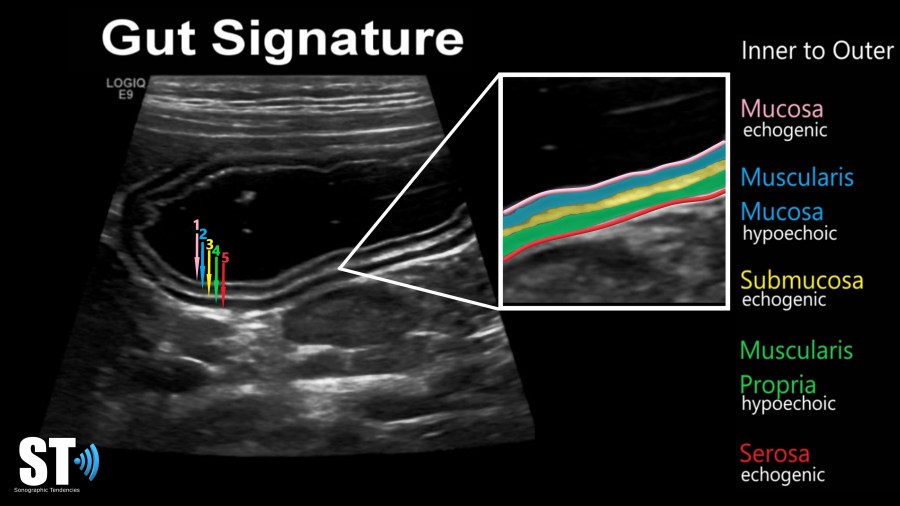

We use the “gut signature” to identify any gastric tissue in the abdomen. Bowel has 5 layers, made up of alternating hyperechoic and hypoechoic layers. These layers correspond to the histology of bowel. The layers are:

- mucosa: echogenic

- muscularis mucosa: hypoechoic

- submucosa: echogenic

- muscularis propria: hypoechoic

- serosa: echogenic